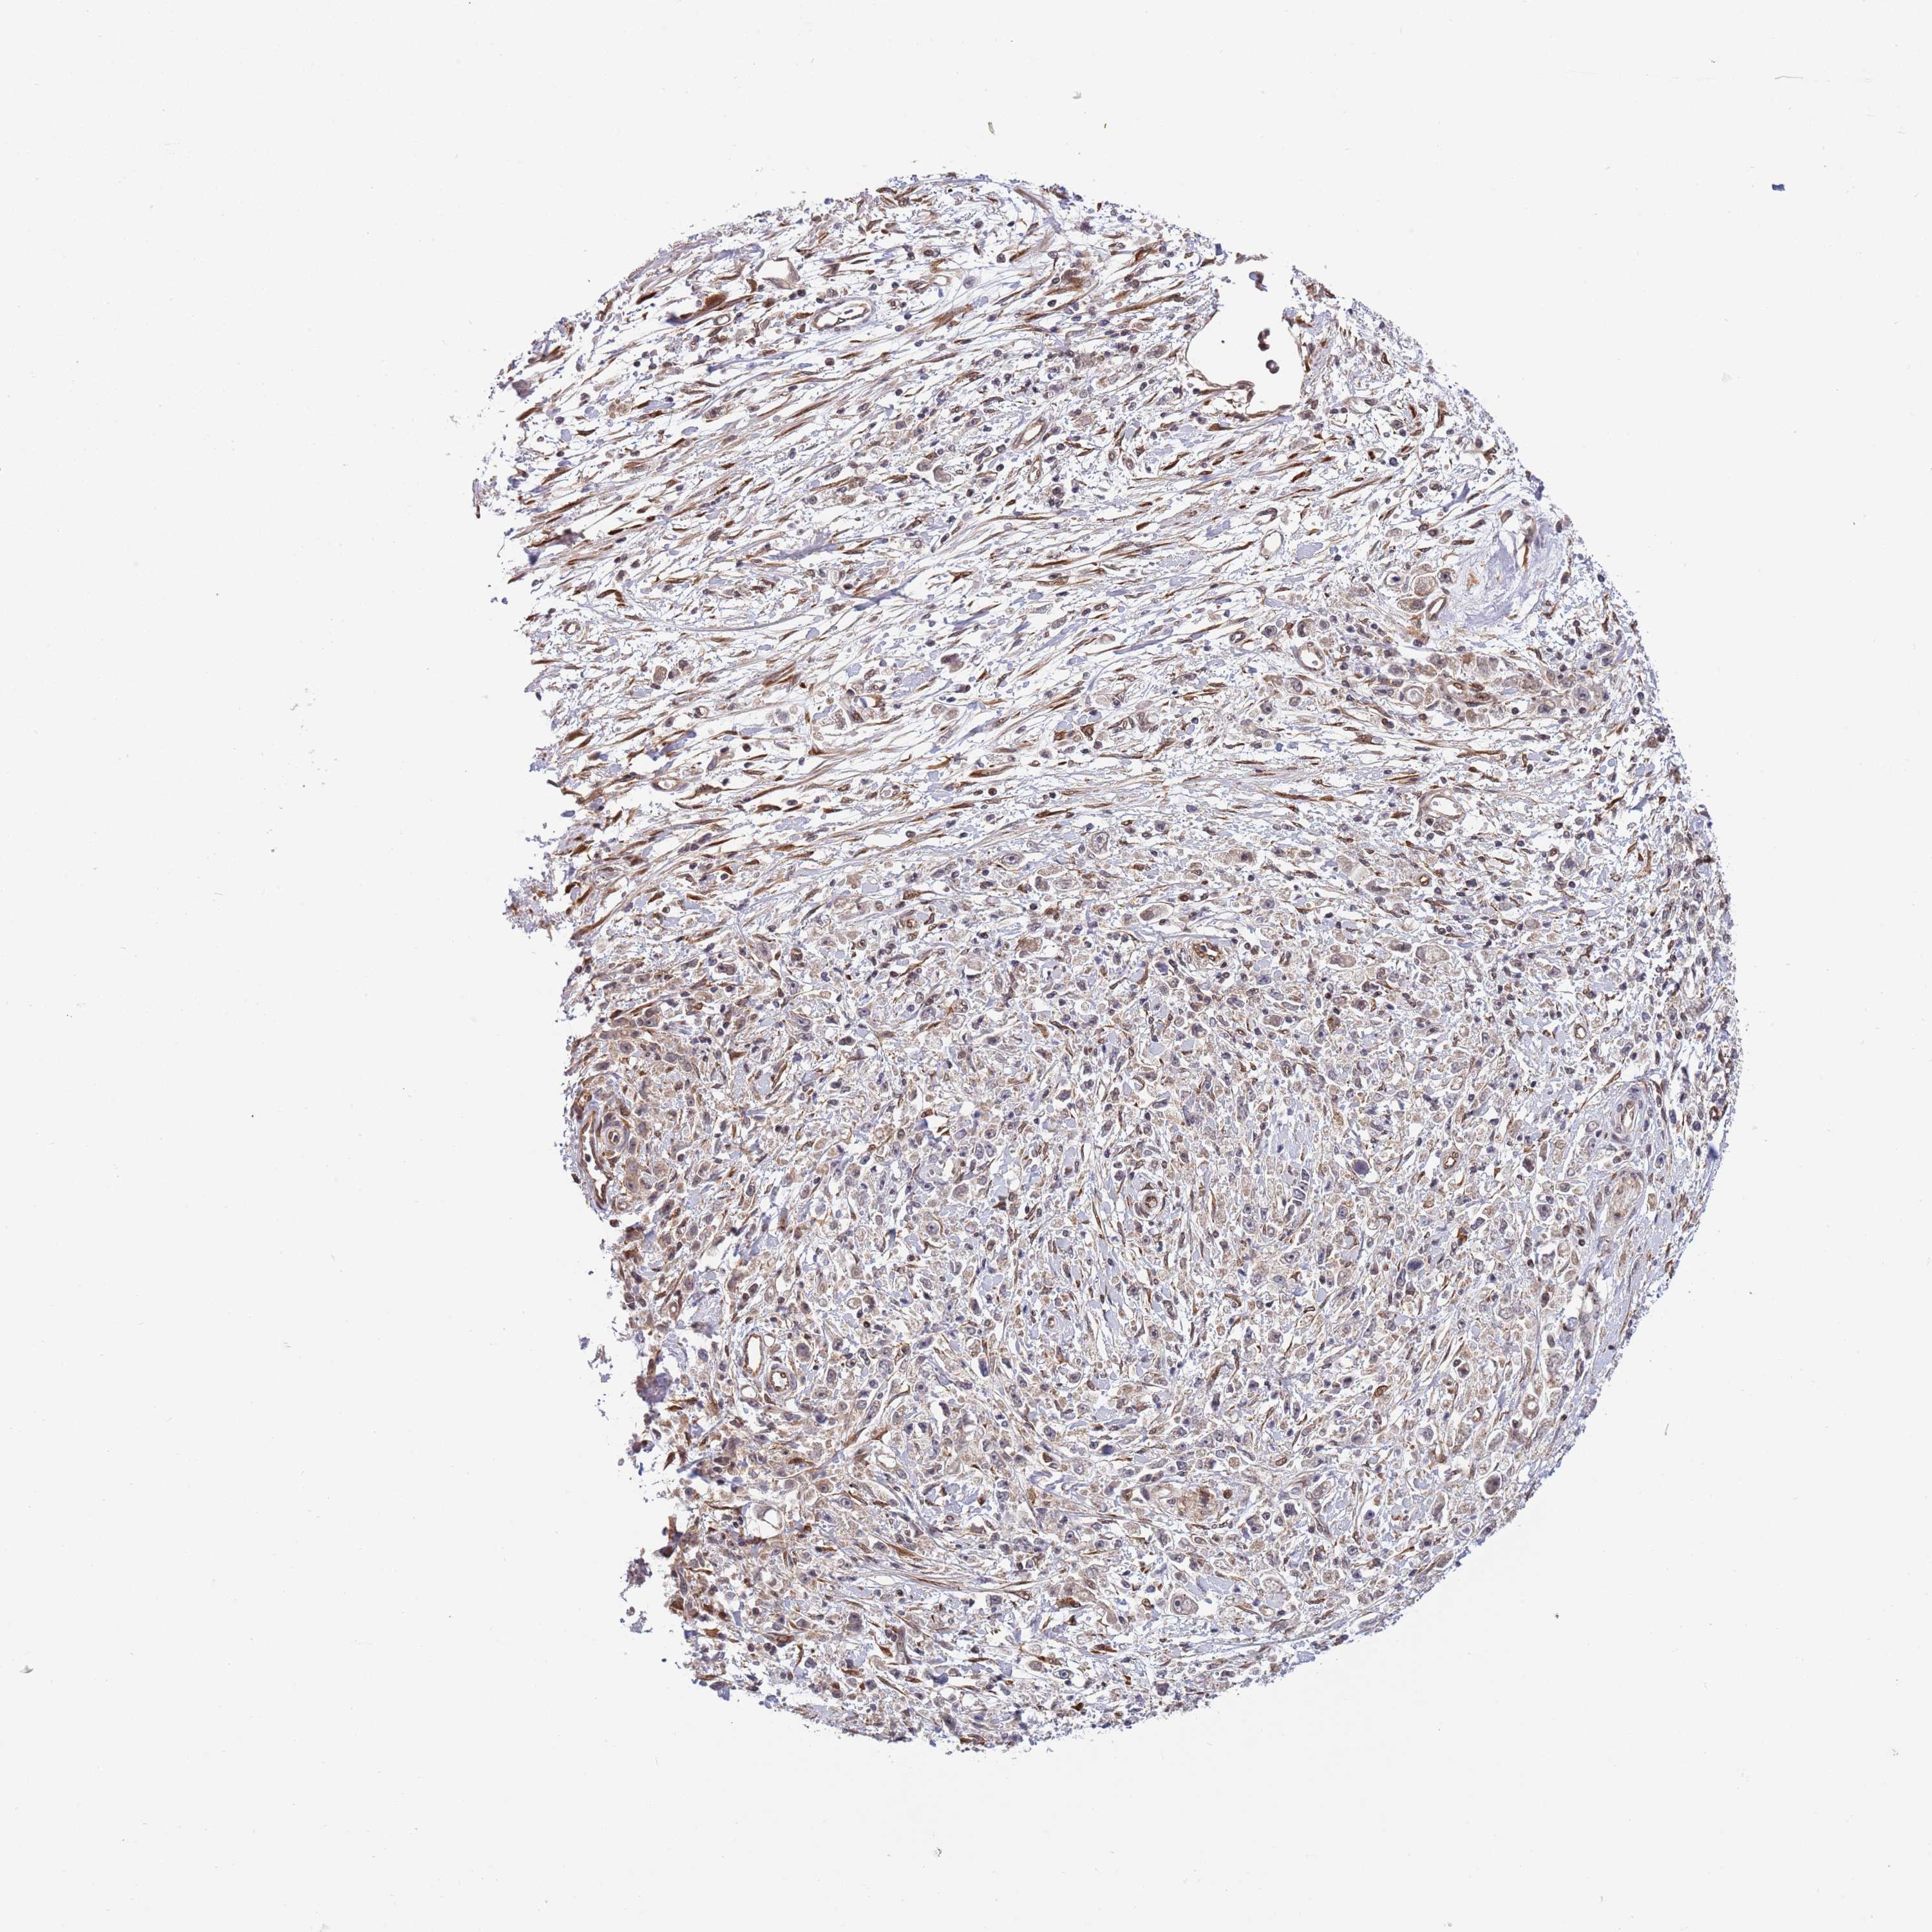

STOMACH CANCER - Protein expressioni

A mouse-over function shows sample information and annotation data. Click on an image to view it in a full screen mode. Samples can be filtered based on level of antibody staining by selecting one or several of the following categories: high, medium, low and not detected. The assay and annotation is described here.

Note that samples used for immunohistochemistry by the Human Protein Atlas do not correspond to samples in the TCGA dataset.

Antibody stainingi

Antibody staining in the annotated cell types in the current human tissue is reported as not detected, low, medium, or high, based on conventional immunohistochemistry profiling in selected tissues. This score is based on the combination of the staining intensity and fraction of stained cells.

Each image is clickable and will lead to virtual microscopy that enables deeper exploration of all samples and also displays staining intensity scores, fraction scores and subcellular localization as well as patient and tissue information for each sample.

Antibody HPA047881

Staining

High

Medium

Low

Not detected

Intensity

Strong

Moderate

Weak

Negative

Quantity

>75%

75%-25%

<25%

None

Location

Nuclear

Cytoplasmic/membranous

Cytoplasmic/membranous,nuclear

Adenocarcinoma, NOS